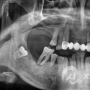

임플란트 치료사례